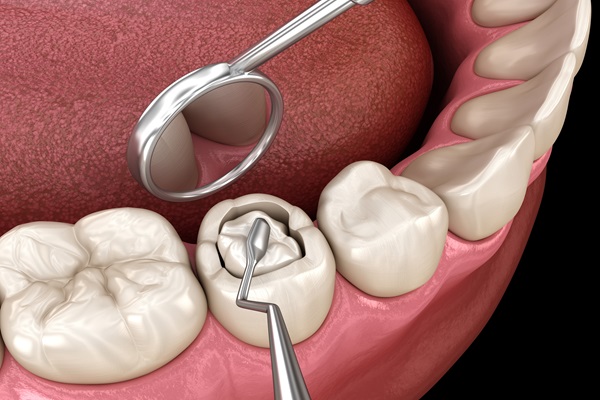

Teeth Restoration / Filling

Fix cavities with strong tooth-colored fillings that blend naturally and last long.